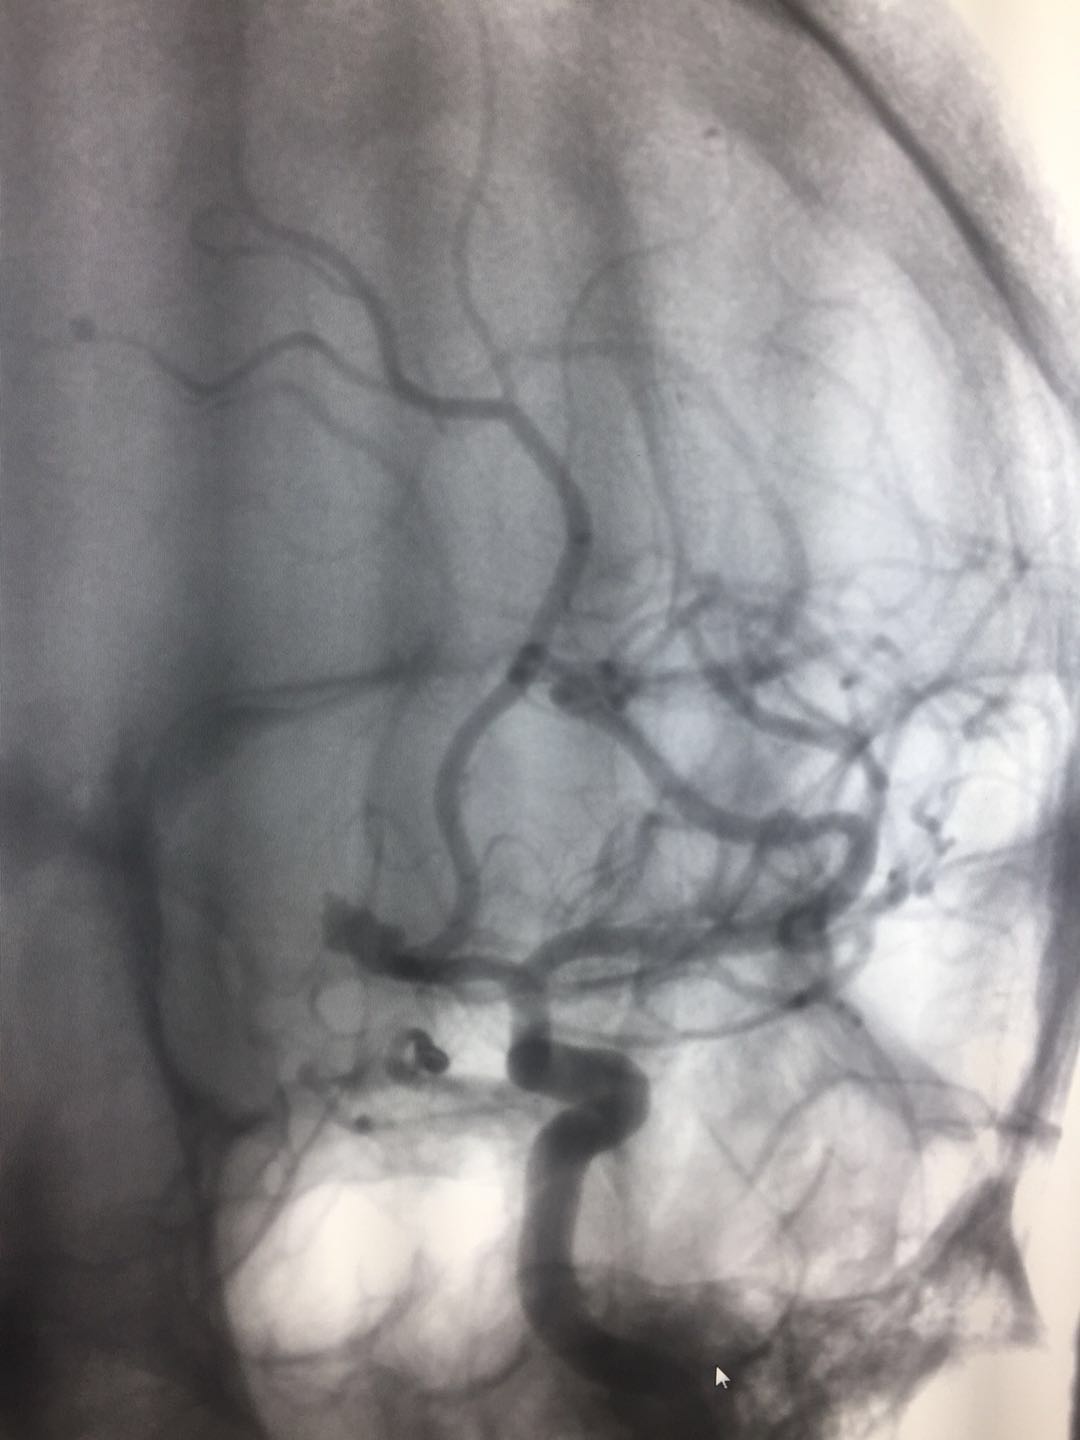

(术中)